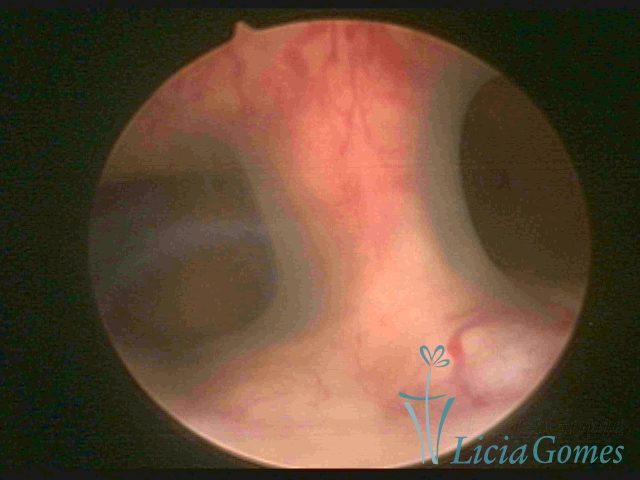

Unicornuate uterus

It presents a tubular cavity with an impaired intracavitary space, resembling the shape of a banana, whose the narrowest edge contains the tubal ostium. The endometrium is compatible with the menstrual cycle and the cervical canal is normal, in structure and trophism.